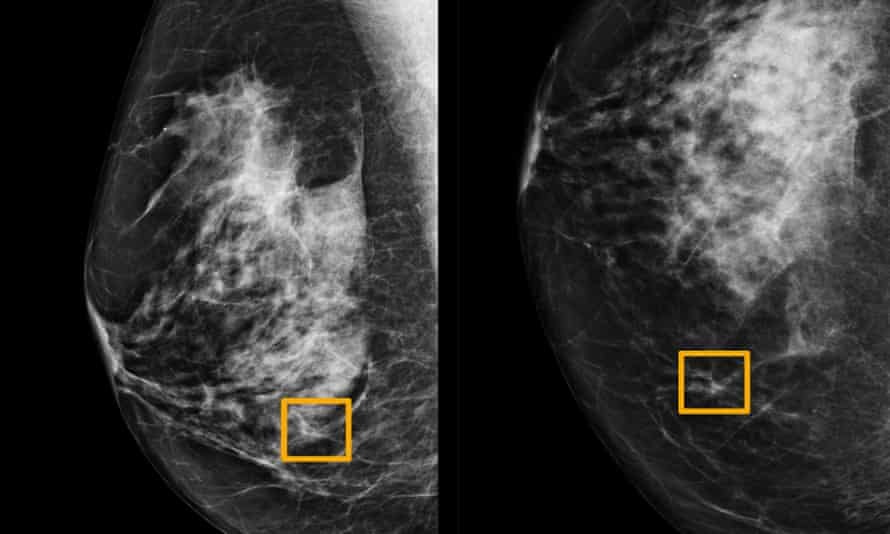

Ung thư vú có dấu hiệu đặc trưng là các khối u ở nách, bầu ngực. Ảnh: The Guardian.

Ung thư vú có thể xuất hiện các triệu chứng khác nhau. Dấu hiệu nhận biết phổ biến nhất là khối u ở vú hoặc nách.